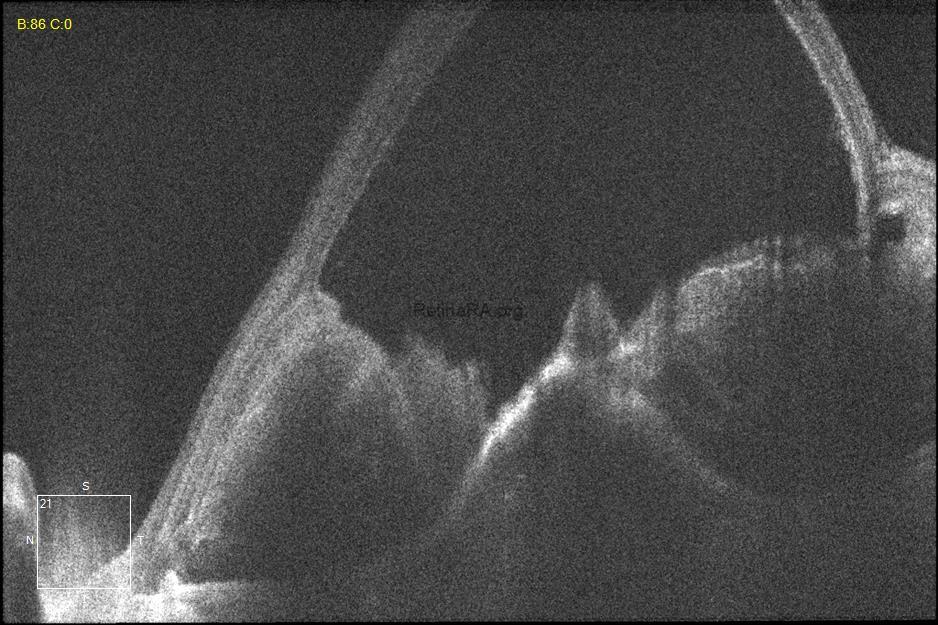

A 71-year-old man with type 1 MNV developed a retinal pigment epithelium (RPE) tear and subsequent massive submacular hemorrhage. At the first visit, his visual acuity was 20/100. There is no sign of a RPE tear on the autofluorescence image. However, OCT scans show risk factors for developing RPE tears, such as high RPE detachment (PED), corrugation of RPE , and prechoroidal cleft. Type 1 macular neovascularization (MNV), subretinal fluid, and subretinal hyperreflective material also appear on OCT.